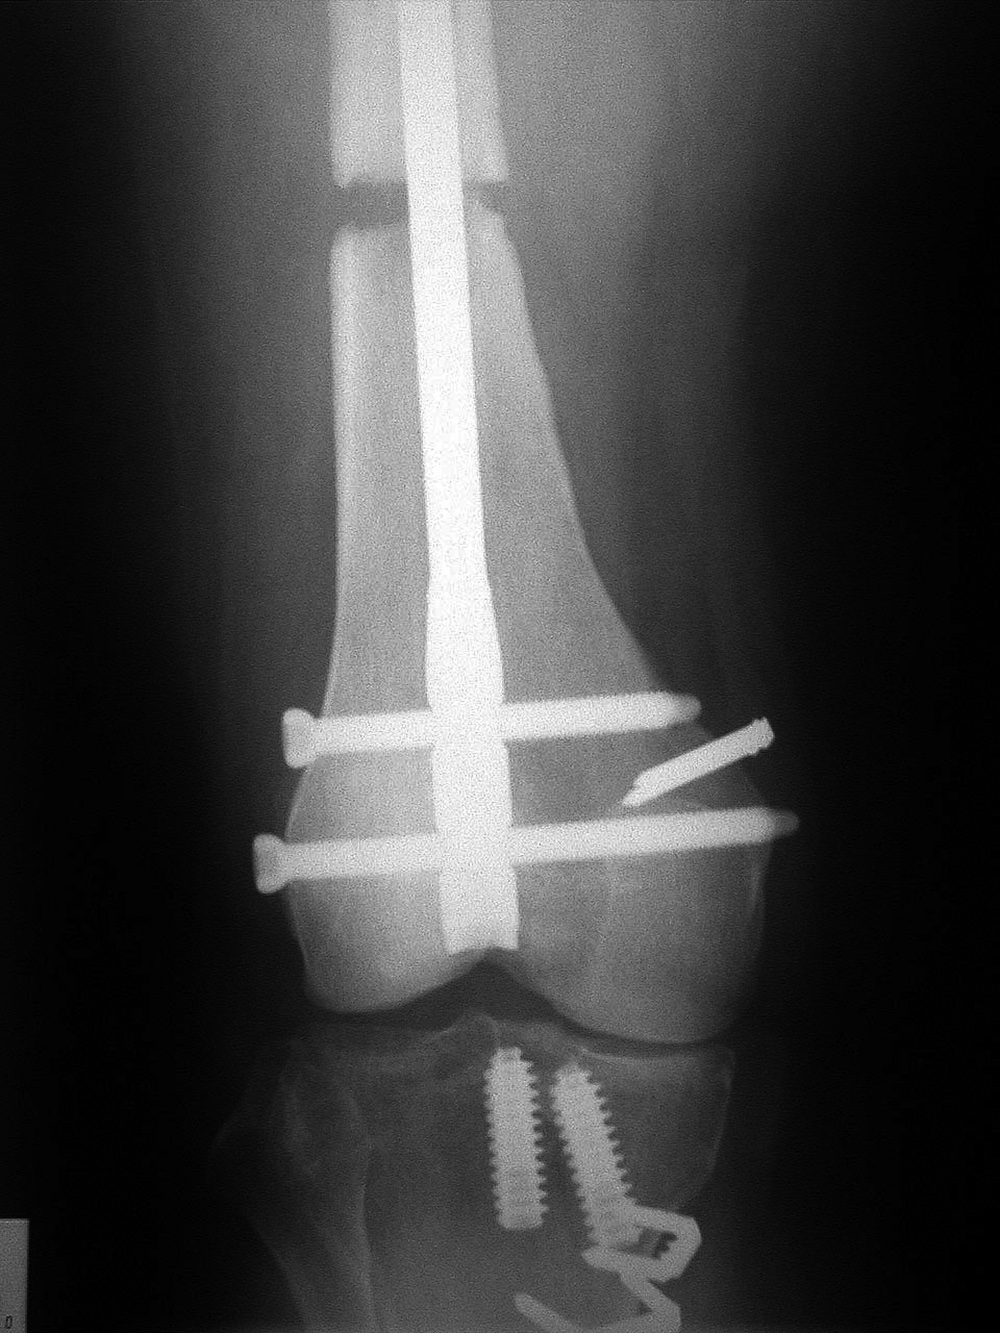

AP and lateral views of the knee show a distal femoral cadevaric limb sparing allograft approximated to the native distal femoral stump by a retrograde intramedullary nail. Two interlocking cannulated screws go through the distal portion of the nail. Cruciate ligament and capsular reattachment were performed with two interference screws and two staples in the proximal tibia and a staple in the posterior aspect of the allograft metaphysis. The patient had a non-specified distal femur sarcoma.